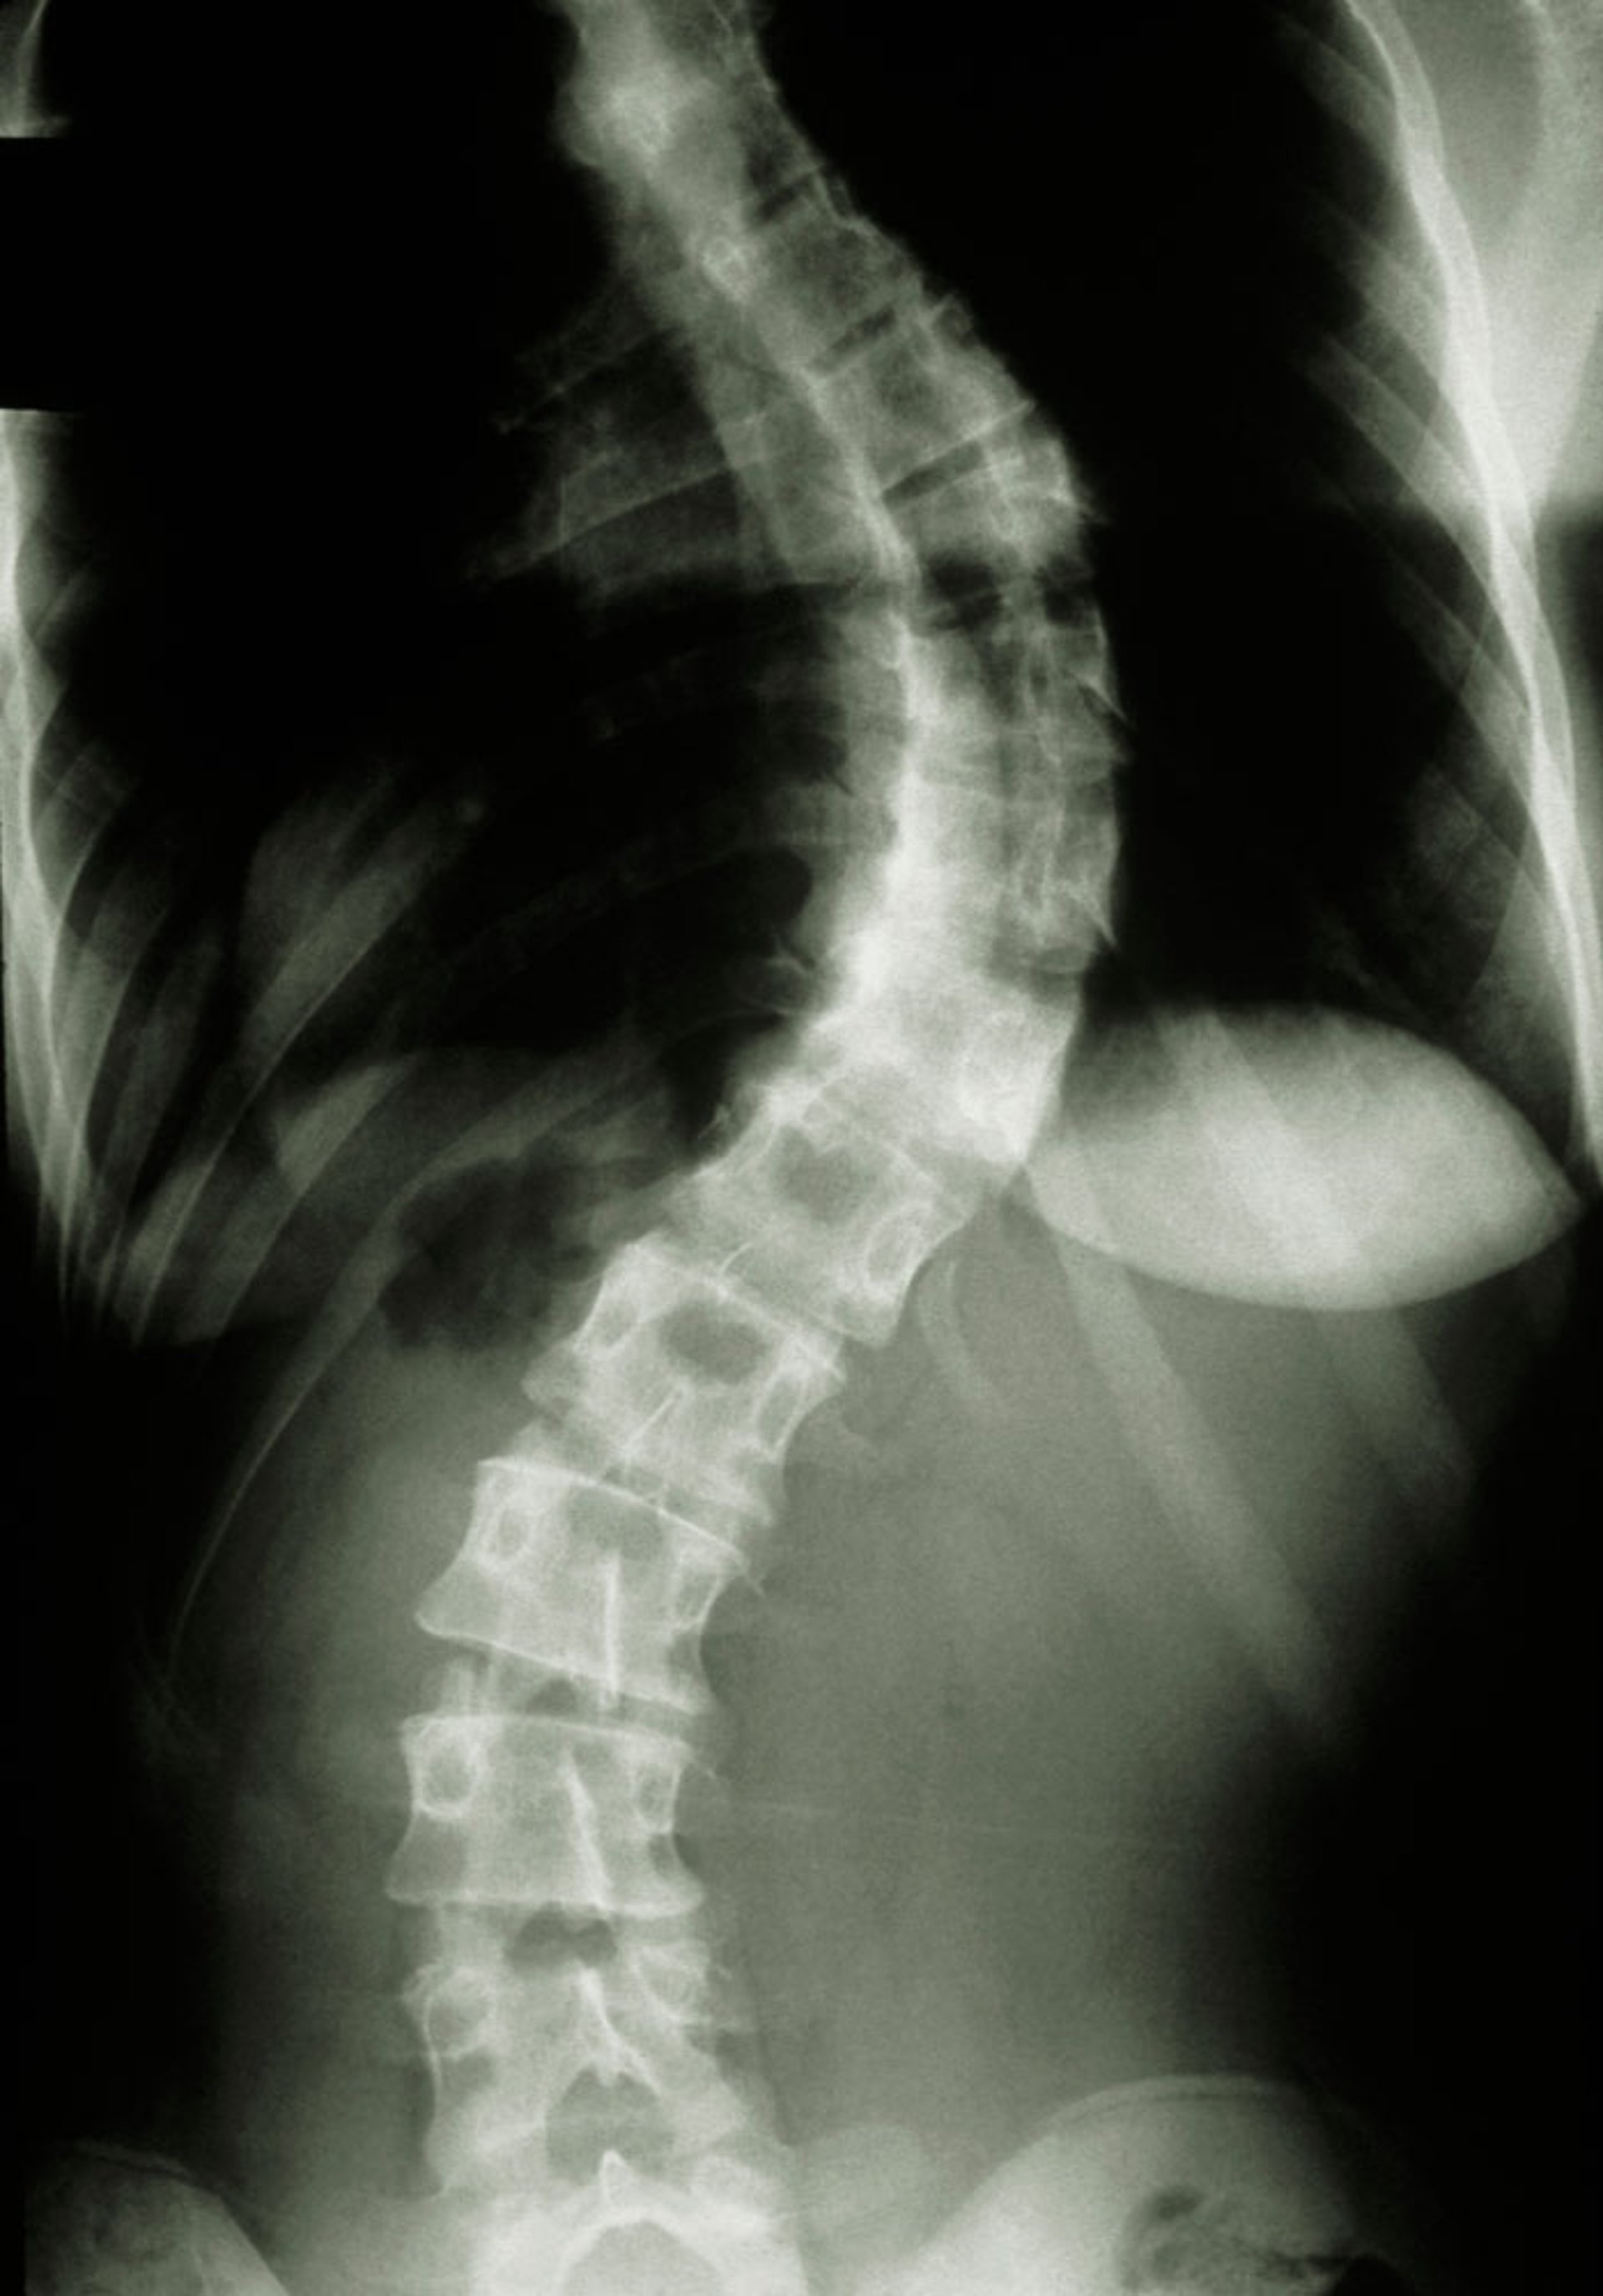

Patients are taller than average for age and family; arm span exceeds height. Arachnodactyly (disproportionately long, thin digits) is noticeable, often by the thumb sign (the distal phalanx of the thumb protrudes beyond the edge of the clenched fist). The chest wall abnormalities pectus carinatum (outward displacement) and pectus excavatum (inward displacement) are common as are joint hyperflexibility, limited elbow extension (though usually small flexion contractures to the elbows), genu recurvatum (backward curvature of the legs at the knees), pes planus (flat feet) or hindfoot valgus, kyphoscoliosis, and diaphragmatic and inguinal hernias. Subcutaneous fat usually is sparse.

Musculoskeletal Manifestations in Marfan Syndrome

This image shows the typical body habitus in an adolescent with Marfan syndrome, including kyphoscoliosis, pectus excavatum, and genu recurvatum.

By permission of the publisher. From Macro R: Atlas of Heart Diseases: Congenital Heart Disease. Edited by E Braunwald (series editor) and RM Freedom. Philadelphia, Current Medicine, 1997.